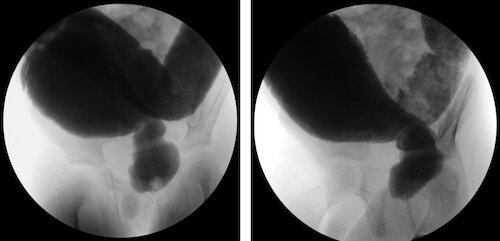

A 4-year-old boy is admitted to the hospital because of a 6-month history of difficulty passing stool. He has no history of serious illness. He receives no medications. Height, weight, and BMI are at the 50th percentile. Vital signs are within normal limits. Physical examination shows a distended, nontender abdomen. Contrast enema imaging is shown. Which of the following is the most appropriate next step in management?